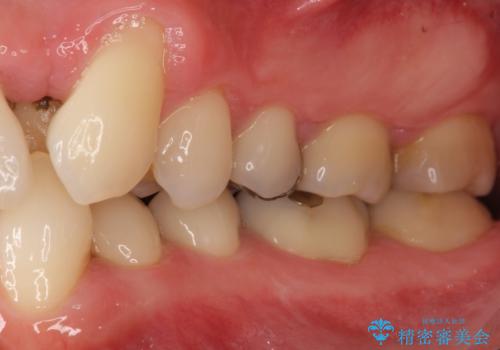

矯正治療とホワイトニングを提案しましたが希望されず、「接客関係の仕事で矯正治療は考えられない、短期間で治療を終わらせたい、ホワイトニングでは難しい位の人工的な白さにしたい」とのご要望により、治療前にワックスアップ模型を作製し何度もコンサルテーションを重ね、治療方針を決定しました。

歯頚ラインが変えられないことや天然歯を削るリスクをご理解頂いた上で、オールセラミッククラウンによる補綴治療を行いました。(見えない奥歯のみ天然歯のままとしました)

クラウンの色味・形態の修正や患者様のお仕事のご都合で来院できない期間があったことにより、予想より治療期間が長くなってしまいましたが、審美的な仕上がりにご満足頂けました。

矯正治療で歯並びを整えたいというのが歯科医師である私の本心でしたが、患者様の強いご希望によりオールセラミッククラウンによる補綴治療を行いました。

クラウンの色味に関して、自然な白さ(シェードA1~NW0.5)のクラウンを作製・試適したところ「もっと白くしたい」と希望され、当院で最も明度の高い色(シェードNW0)に修正しました。

被せ物の種類:オールセラミッククラウン スタンダード (シェード:NW0)